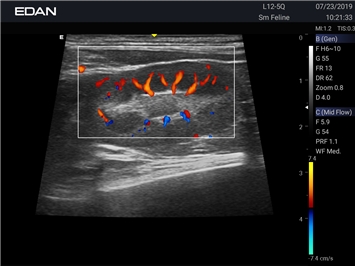

УЗИ-аппарат

EDAN Acclarix AX8 VET

Новая эра УЗИ в ветеринарии. Диагностическая ультразвуковая система для ветеринарии, AX8 — это многофункциональная диагностическая ультразвуковая платформа с расширенными режимами визуализации, двумя сенсорными экранами с жестовым управлением и полным набором датчиков, которые соответствуют конкретным потребностям ветеринаров.

Профессиональный ветеринарный УЗИ аппарат EDAN Acclarix AX8 VET сочетает инновационные технологии визуализации с надежной конструкцией, специально разработанной для ветеринарной практики.

Цветовой допплер:

Да

Энергетический допплер: